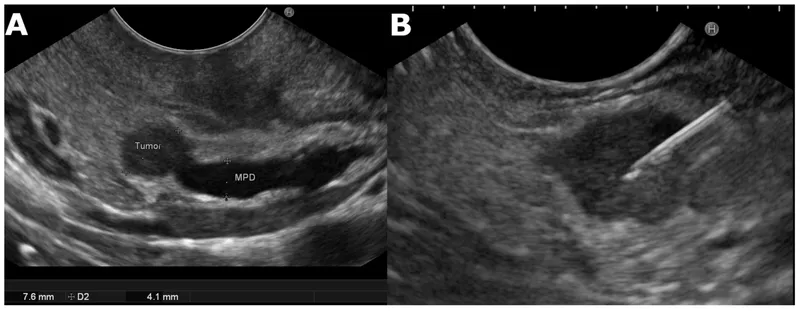

- Localization: Endoscopic ultrasound (EUS) is gold standard. CT/MRI.